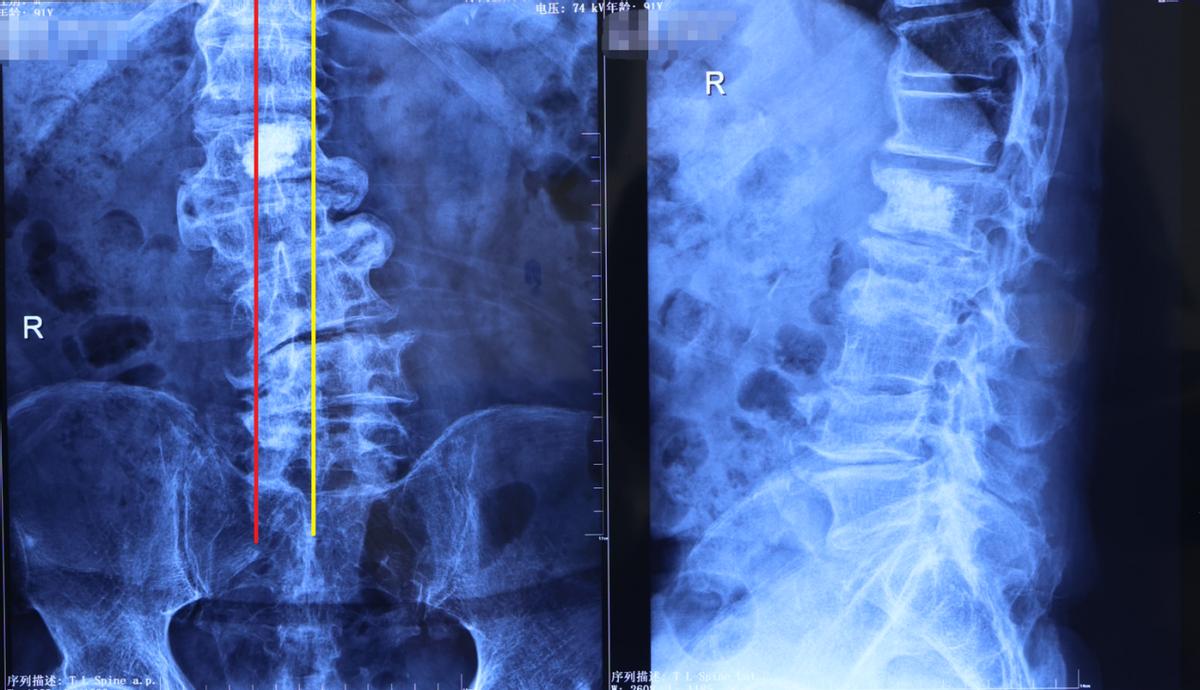

1、脊柱侧弯:冠状位失平衡,出现腰背部慢性疼痛

从这位老人的片子上,可以很清晰地观察到他的腰椎发生了侧弯。我们从骶骨往上打一条中线(下图黄色线条),再从胸腰椎往下打一条中线(下图红线),这两条线是错开的。但是健康人群的这两条线应该是重合的直线,或者相差不大。

这就说明这位老人的脊柱力线不平衡,也就是我们临床所说的冠状位失平衡。这种情况下,老人腰椎的双侧肌肉是不对称的,而且腰部和背部会出现较严重的慢性疼痛。